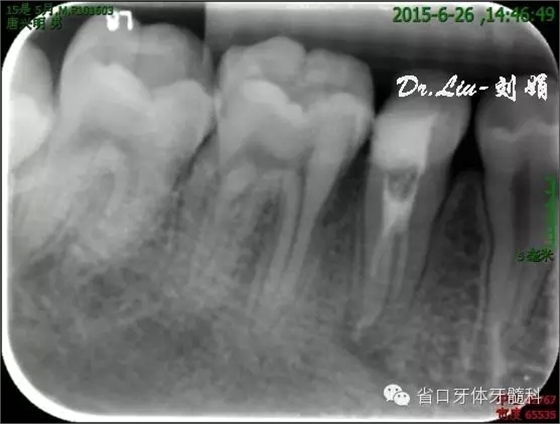

圖8:1月后復(fù)診根尖低密度影有消退趨勢(shì)

根管充填:

45橡皮障隔離下去封藥,清理根管,沖洗,紙尖干燥根管,拍攝試主尖片,顯微鏡下行熱牙膠根管充填,X線片顯示恰填。